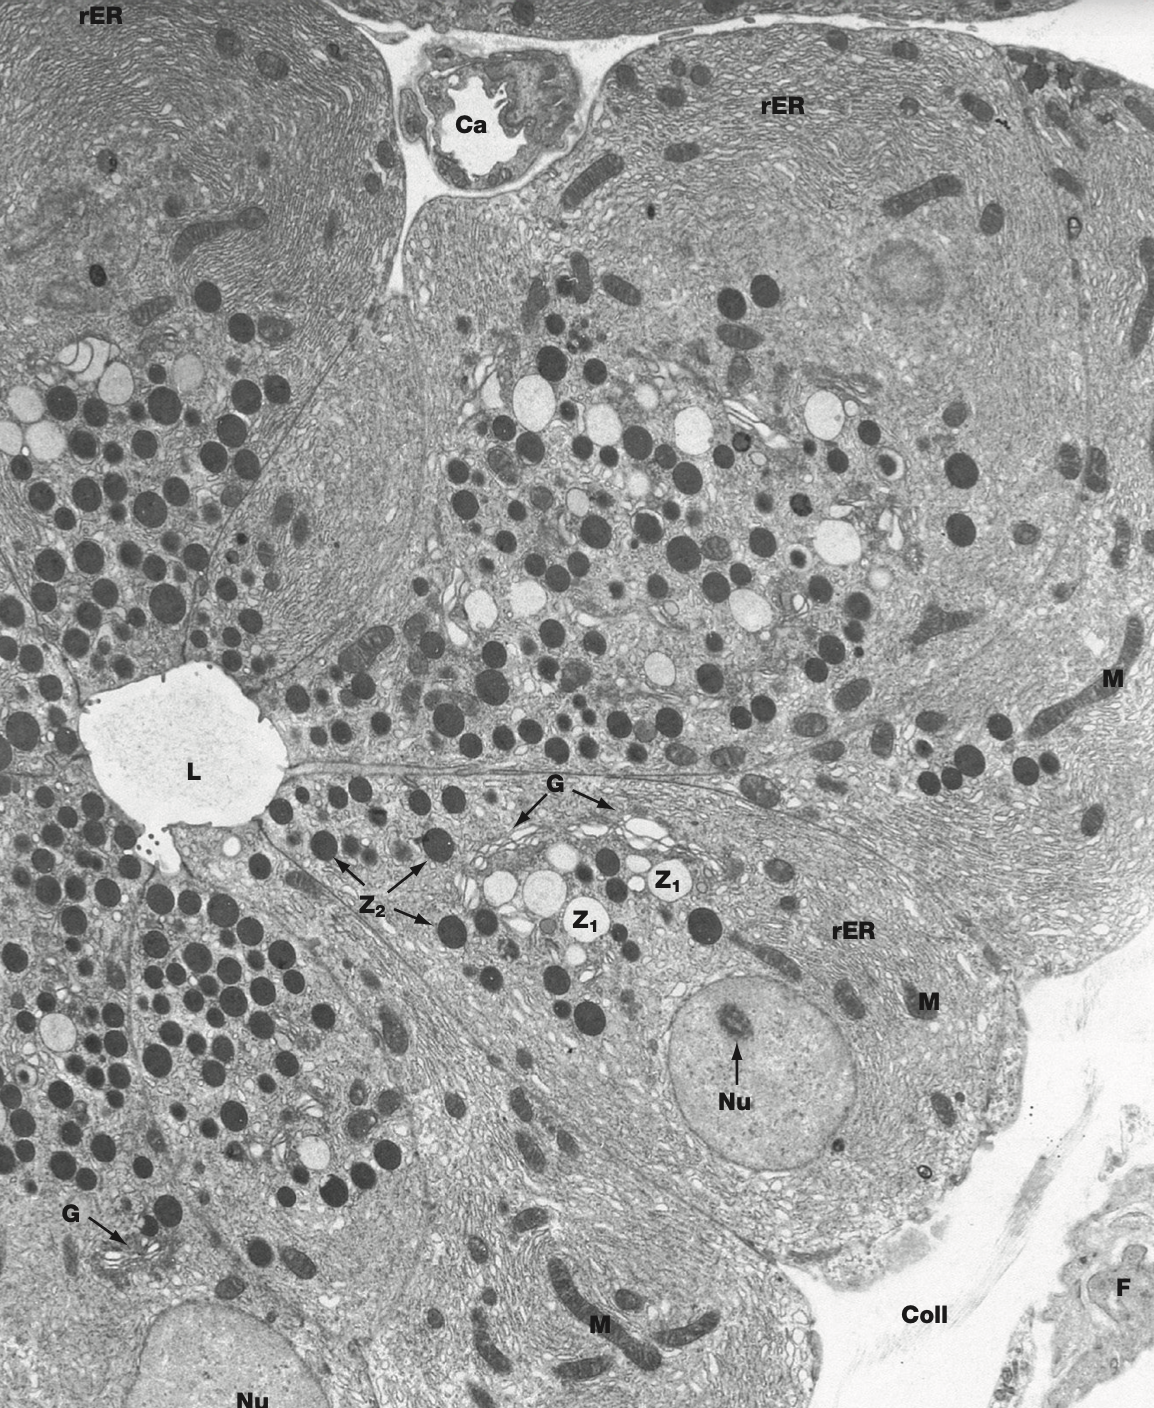

Liver; MV of hepato next to dark on the L, D = space of Disse, L of cow print is endothelium of suni